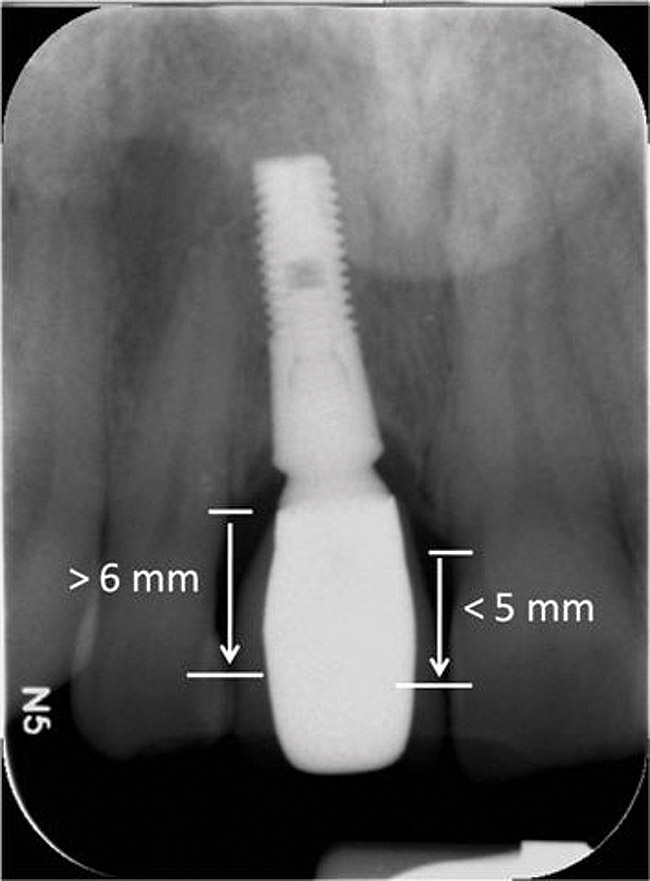

Figure 4 Characterization of the interproximal bone and tooth contacts: A periapical radiograph assists in measuring the distance from bone crest to the adjacent tooth contact points for missing tooth No. 8. The mesial bone crest to the adjacent tooth con

Figure 4

Figure 5 Characterization of the interproximal bone and tooth contacts: A periapical radiograph assists in measuring the distance from bone crest to the adjacent tooth contact points for missing tooth No. 8. The mesial bone crest to the adjacent tooth con

Figure 5

Additional attention must be paid to the osseous architecture related to the adjacent teeth, as this controls interproximal tissue form.7 The crest of healthy bone is 4.5 mm to 5 mm from the contact point between anterior teeth8; a similar 5-mm distance from the contact point to the bone crest has been measured between an implant and natural tooth. An important and additional rule to guide esthetic implant outcomes is that the adjacent tooth should possess interproximal bone levels no further than 6 mm from the natural tooth contact point (Figure 4 through Figure 6). While the ideal distance is justifiably indicated to be 5 mm, this 6-mm rule establishes a point at which marked interproximal tissue deficiencies and asymmetry will not be overcome.

In the context of the Rules of Six, the single periapical radiograph offers several advantages. Within a periapical radiograph, the essential features of a single-tooth-bound edentulous space can be observed. In addition to noting any contraindicating potential pathology, the periapical radiograph can indicate bone quality and bone quantity. A periapical radiograph can demonstrate the inter-radicular dimension. It also demonstrates the level of osseous attachment at adjacent teeth, suggesting the presence of clinical loss of attachment or therapeutic recession. This radiographic representation is ideal for measuring the distance from the interproximal contact to the bone crest (Figure 4). It will further suggest adjacent tooth health and status (eg, periapical lesions, fractures, existing endodontic therapy, quality of post-and-core restorations, recurrent caries). Unfortunately, periapical radiographs do not demonstrate these structures in the saggital (or coronal) planes.